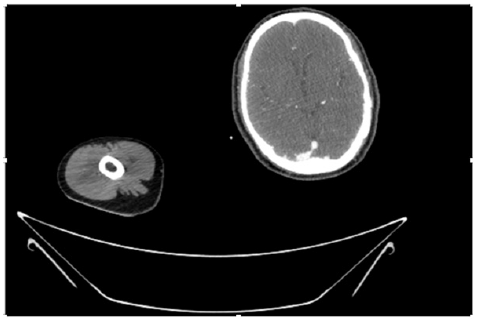

55-years-old chronic smoker had acute, severe pain in the right upper limb for one week; it was cold upto mid arm with skin discoloration. He also noticed numbness and weakness of movement of elbow joint. He underwent below elbow amputation in February 2023 for acute ischemia of left upper limb. He was a current chronic smoker; 15 pack year. General condition was weak; temperature was normal; blood pressure was 100/60mmHg; heart rate was 92/minutes with sinus rhythm; SpO2 was 97% on air; heart was normal. In lower extremities, all peripheral pulses were intact. Local Examination of right upper limb revealed as follows: tenderness; coldness; discoloration; decreased motor function and sensory modalities. Axillary, brachial and radial pulses were not palpable. Hand-held Doppler failed to detect any signal in arterial system; therefore, we arranged for emergency embolectomy. complete occlusion of right upper limb arterial system Full blood count showed high hemoglobin (14.6gm%); normal total WBC and platelet count. Coagulation profile was normal. Parenteral unfractionated heparin, antibiotics, tramadol, proton-pump inhibitors, anti-platelets and HMG CoA reductase inhibitors were given. Doppler ultrasound demonstrated complete occlusion of right upper limb arterial system. CT Angiogram illustrated occlusion of subclavian artery downwards on both sides. Figures 1-14 shows complete occlusion of right subclavian artery without collaterals. On Day ‘2’ of admission, the patient passed black tarry stool for 3 times. However, the vital signs were stable; blood pressure was 100/60mmHg; heart rate was 92/min; SpO2 was 97% on air; the abdomen was soft and not tender. Above elbow amputation was done on Day ‘2’ of admission. Intra-operative findings were as follows: (1) no active bleeding at brachial artery; (2) thrombosis along brachial artery; (3) muscle color and consistency were not healthy.

Figure 4: CT Angiogram at neck showing normal brachio-cephalic trunk, common carotid artery, and narrow right subclavian artery.

Figure 5: CT Angiogram at neck showing normal brachio-cephalic trunk, common carotid artery, and narrow right subclavian artery.

Figure 6: CT Angiogram at neck showing brachio-cephalic trunk, common carotid artery and narrow right subclavian artery.

Figure 7: CT Angiogram at neck showing brachio-cephalic trunk, common carotid artery and narrow right subclavian artery.

Figure 10: CT Angiogram at upper arm showing totally occluded right axillary artery; normal internal carotid artery and external carotid artery.